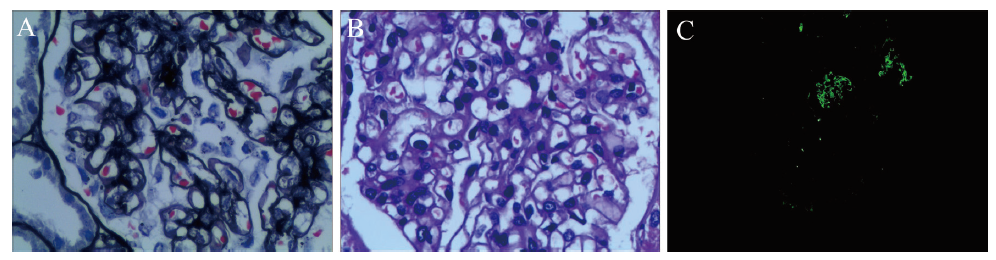

患者男, 34岁。因“反复多尿、四肢乏力10年, 再发1 d”于2017年2月15日入我院内分泌科。10年前曾出现四肢酸痛、乏力、多尿(日尿量2700~3000 mL)、夜尿多(夜尿1~3次/日), 查血钾低, 尿蛋白阴性, 血白蛋白41 g/L, 估算肾小球滤过率(eGFR) 118 mL/(min·1.73 m2), 肾素、醛固酮、皮质醇、甲状腺功能未见异常, 诊断“低钾血症”, 经补钾治疗后症状缓解。患者仍反复出现四肢乏力, 每次自行服用钾剂后症状均可缓解。5年前患者上述症状再发加重, 伴双下肢水肿, 至当地医院治疗, 多次查血钾偏低, 波动在2.37~2.90 mmol/L, 尿蛋白20.9 g/24 h, 行肾活组织检查(活检)示“原发系膜增生性肾小球肾炎”(图1)。予应用激素、补钾等治疗, 症状缓解出院。1 d前再次出现四肢乏力, 不能行走, 伴下肢水肿, 为进一步诊治收入我院。

图1 原发系膜增生性肾小球肾炎合并肾小管酸中毒患者肾活检病理检查结果

注:A为过碘酸六胺银染色(×400);B为过碘酸希夫染色(×400);C为IgG沉积于系膜区。